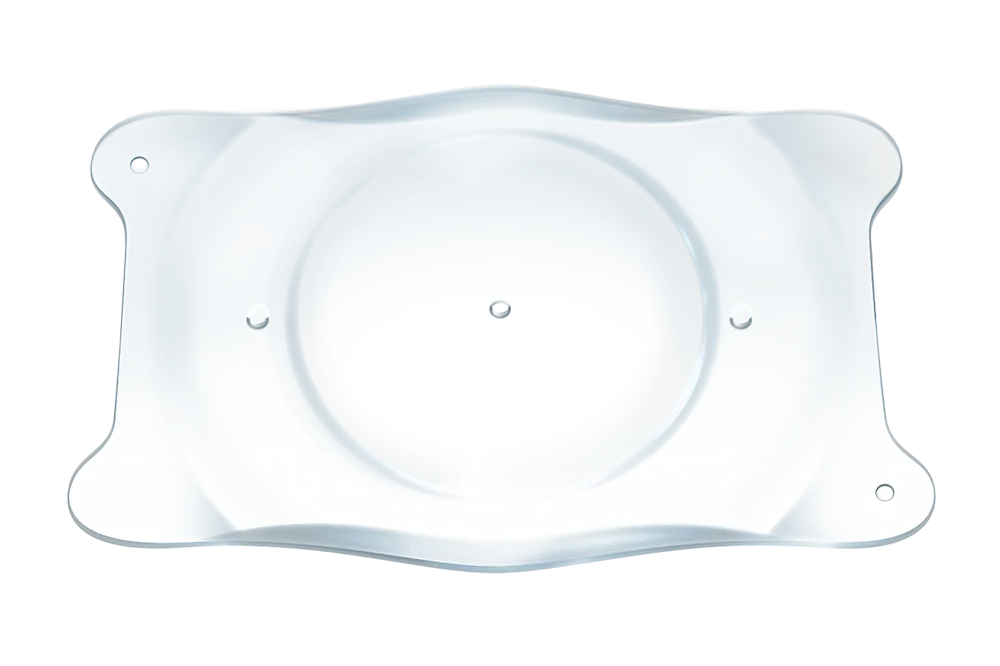

- EVO ICL is een phake lens.

- EVO wordt direct achter de iris en vóór de natuurlijke kristallijne lens geplaatst.

- De toevoeging van de centrale aqua port bij EVO vergemakkelijkt de stroom van aqueous humor doorheen de lens.

- De EVO-lens is een reversibel implantaat.